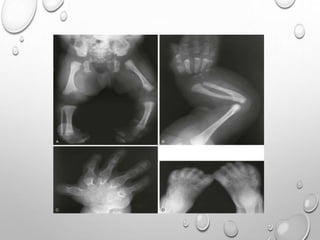

SHORT , VENTRALLY BOWED TIBIA , FEMUR , HYPOPLASTIC OR

ABSENT FIBULA

TALIPES EQUINOVARUS , CDH

MICRODACTYLY OF IST TOE ..75% CASES , SOMETIME THUMB

( ABSENCE , SHORT PHALANX , SYNOSTOSIS)

HALLUX VALGUS

CLINODACTYLY